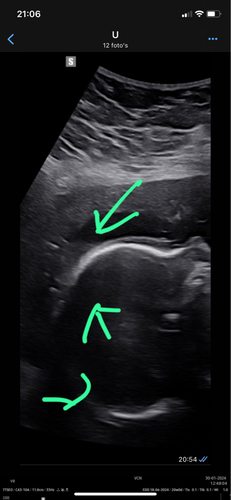

Zie je hier ook haartjes, of kijk ik naar heel iets anders? 馃槅